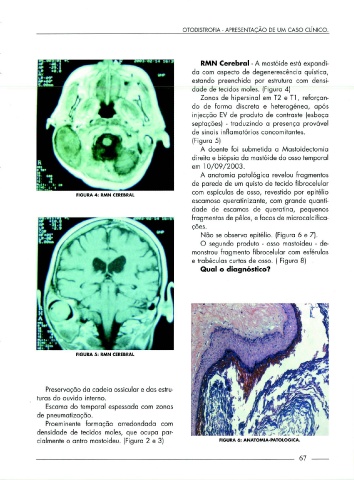

RMN Cerebral - A mastóide está expandi-

da com aspecto de degenerescência quística,

estando preenchida por estrutura com densi-

dade de tecidos moles. (Figura 4)

Zonas de hipersinal em T2 e Tl, reforçan-

do de forma discreta e heterogénea, após

injecção EV de produto de contraste (esboça

septações) - traduzindo a presença provável

de sinais inflamatórios concomitantes.

(Figura 5)